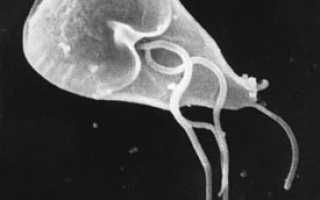

image Трофозоит лямблии под сканирующим электронным микроскопом

Лямблии, как и другие дипломонады, имеют два ядра и двойной набор органоидов — четыре пары жгутиков и два медиальных тела. Само тело имеет грушевидную форму: передний конец расширен и закруглён, задний — сужен и заострён. Для этого рода характерен сложно устроенный прикрепительный диск, а также полное отсутствие цитостома. Размеры тела от 10 до 18 мкм. Способны образовывать цисты. Зрелые цисты имеют овальную форму и 4 ядра.Через середину тела проходят две опорные нити — аксостили, около которых расположено парабазальное тельце. Лямблии — анаэробы. Они лишены митохондрий и аппарата Гольджи. У них обнаружены рудиментарные митохондрии — митосомы, имеющие двойную мембрану и снабжаемые белками тем же способом, что и митохондрии (см. Внутриклеточная сортировка белков), но лишённые генетического материала.

Вегетативная форма активная, подвижная, грушевидная, передний конец тела закруглен, задний заострен. Длина 9—18 мкм. В передней части тела находится присасывательный диск в виде углубления. Имеет 2 ядра, 4 пары жгутиков. Жгутики, проходя частично в цитоплазме, образуют два хорошо видимых при окраске продольных пучка.